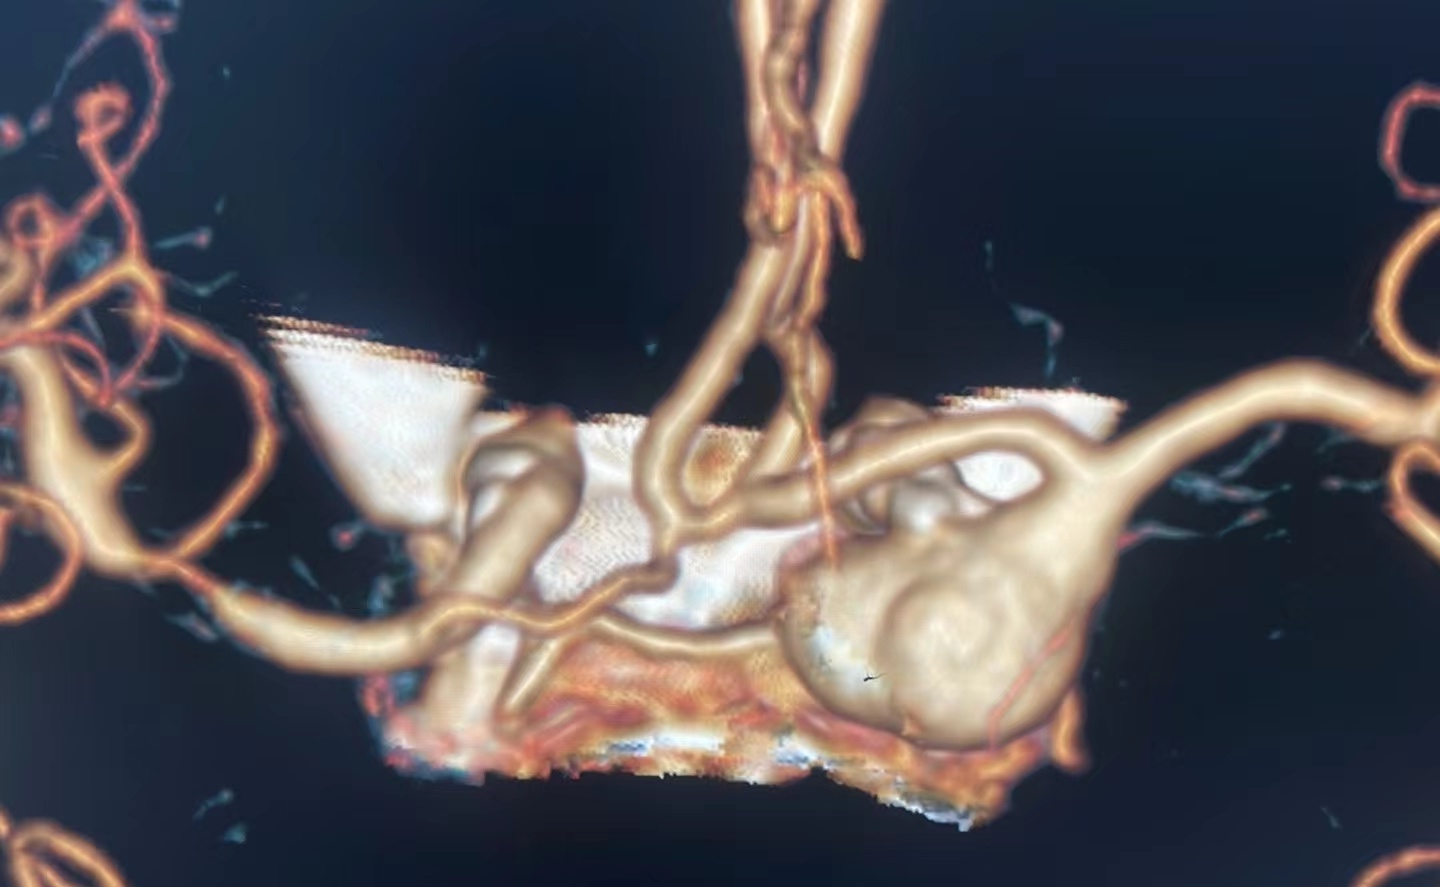

CTA可见左侧颈内动脉颅内段巨大动脉瘤,瘤体12.5*14*9mm。

左侧颈内动脉C7动脉瘤改变。